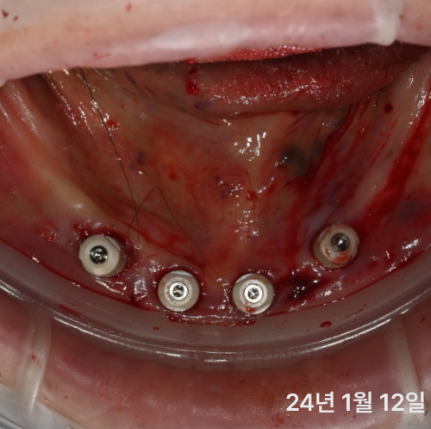

대부분 앞쪽에는 뼈가 있어서

틀니 오래 끼신 분도

이렇게 기존에서 심으면 가능한 경우가 많아요

더군다나 디지털 가이드를 이용해서

뼈가 얇은 경우에도 정확하게 심을 수 있어요